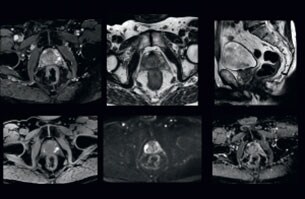

• Smart Reading cloud based reporting

Smart Reading

Automated quantitative AI cloud-based reporting for prostate and neurological diseases like Alzheimer and Multiple Sclerosis.